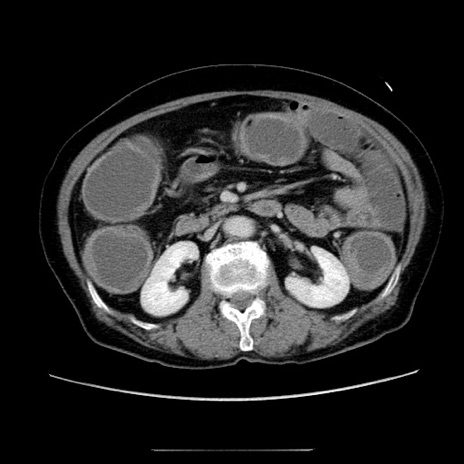

症例5(横断像)

【症例】70歳代女性

【主訴】お腹が張る

【現病歴】1週間くらい前から腹部膨満の自覚あり。昨日夜から増悪したため、本日救急外来受診。

【身体所見】意識清明、BT 36.5℃、BP 165/106mmHg、HR 80bpm、SpO2 98%、腹部:膨満、軟、自発痛・圧痛なし、触診にて不快感あり、腸蠕動音:減弱

【データ】WBC 12600、CRP 1.04